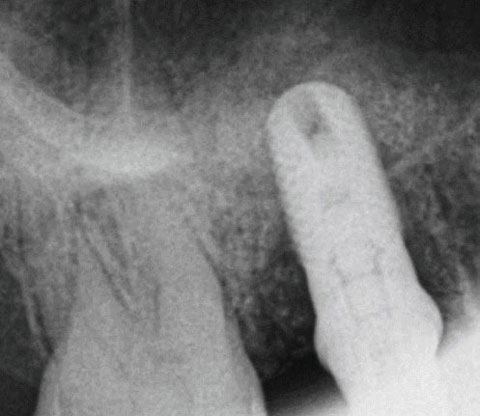

Applikation von OSSIX™ Bone in eine Extraktionsalveole ohne Lappenpräparation: Nach der Zahnextraktion (li) wird OB mit Defektblut getränkt (Mi) und vorsichtig bis zum krestalen Level in die Alveole eingebracht (re). Mit freundlicher Genehmigung von Dr. Fred Silva, USA.